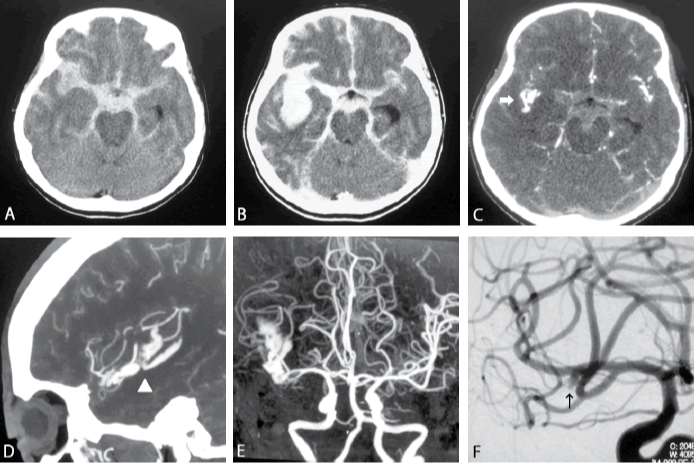

脑动脉瘤治疗方法包括两种,一种是开颅手术夹闭,外科医生通过开颅手术使动脉瘤暴露,并在动脉瘤的底部放置一个金属夹,以使血液无法进入动脉瘤。另一种是血管内栓塞治疗,是指在血管内放置一个或多个微小的铂金线圈,导致其中的血液凝结并损害了动脉瘤。

有的病人临床症状很轻,但CT、MRI及血管造影(用对比剂)可能显示血脑屏障或血脑脊液屏障有障碍及血管痉挛,这些是潜在脑损伤的重要现象。动物试验在蛛网膜下腔出血后2~4h,即可查出广泛血脑屏障受损,表现为血流及代谢障碍,尽管其临床症状很轻。

INC国际神经外科医生集团提醒,目前的显微手术技术已达到相当高的程度,既然颅内动脉瘤的较大危害是一次乃至多次出血造成的,并非由于外科手术,所以建议应着重发现未出血的动脉瘤,及时给予处理。影像学的进一步发展,将能帮助解决这个问题。目前的MRA不需要造影剂,即能显示出全部脑血管影像。有些病种如多囊肾、主动脉缩窄和结缔组织病等容易伴发脑动脉瘤,及时检查将会有所发现。